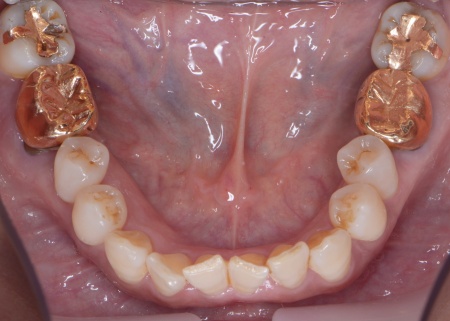

| カウンセリング | 拝見したところ、上下左右の奥歯計8本(第1大臼歯、第2大臼歯)に重度の歯周病が認められました。 歯周病は歯を支えている骨や歯ぐきに炎症が起こる病気です。進行すると歯がぐらついたり、噛む力が弱くなったりします。 さらに悪化すると歯を失う可能性が高くなるだけでなく、周囲の歯にも影響が広がることがあります。 特に下の奥歯2本(左右第1大臼歯)は歯を支えている骨が著しく減少して歯が大きく揺れており、治療して温存することは難しい状態でした。 また、左上の奥歯(第1大臼歯)は過去に詰め物で治療されていましたが、その下で虫歯が再発しています。 以上のことから、下左右の第1大臼歯は抜歯後に歯を補う治療、その他奥歯の治療、再発した虫歯の治療が必要と診断しました。 |

診断結果を踏まえ、まず下左右の第1大臼歯については抜歯したあとにインプラントで補う方法を提案しました。

さらに虫歯が再発していた左上奥歯については、虫歯をしっかりと取り除いたうえで被せ物による修復治療を提案しました。 それぞれのメリット・デメリットを丁寧に説明したところ、治療計画に同意いただきました。 まず、歯周基本治療から開始しました。 下左右の第1大臼歯を抜歯し、その部位にインプラントを埋め込む手術を行いました。同時に、インプラントの隣にある下の第2大臼歯に対して歯周組織再生療法を施しています。 また、左上の奥歯は虫歯を取り除いたあと、歯の形を整えて型取りを行い、最終的にジルコニアクラウンを装着しています。 段階的に治療を進め、すべての治療を終了しました。 |